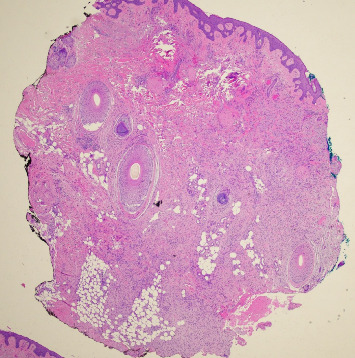

Dermatofibrosarcoma protuberans (DFSP) is a rare, slow-growing soft tissue tumor affecting the dermis and subcutaneous tissues, with potential involvement of muscle and fascia. This case report describes a 68-year-old Caucasian male with a history of recurrent DFSP on the left cheek, initially excised 36 years ago, with multiple recurrences despite wide local excisions (WLEs), eventually requiring left orbital enucleation, presenting to the clinic with a 10-year history of a slow-growing lesion on the left temporal scalp. Examination revealed a 2 cm flesh-colored, firm nodule, which biopsy confirmed as DFSP. Despite two subsequent WLEs, positive margins persisted. The patient refused further surgical intervention and was referred for imatinib and radiation therapy, which he also declined. MRI revealed additional nodules near the left zygomatic arch and sternocleidomastoid. DFSP is diagnosed via biopsy, often confirmed with CD34 immunohistochemistry. Optimal treatment is Mohs micrographic surgery (MMS), but WLE is also used. The recurrence rate is high, especially in head and neck locations. This case underscores the necessity for multidisciplinary management and highlights the critical role of thorough physical and histopathologic examinations. Close clinical follow-up is essential due to the high recurrence risk within the first three years post-treatment. This report emphasizes the importance of early detection and comprehensive care strategies to manage DFSP effectively.